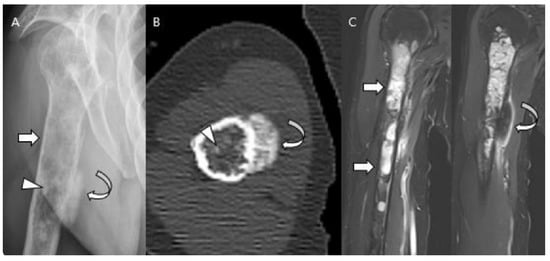

3.3. Distinction between ACT/CS1 and High-Grade Chondrosarcoma

2.3. Third Stage: Central vs. Peripheral vs. Periosteal